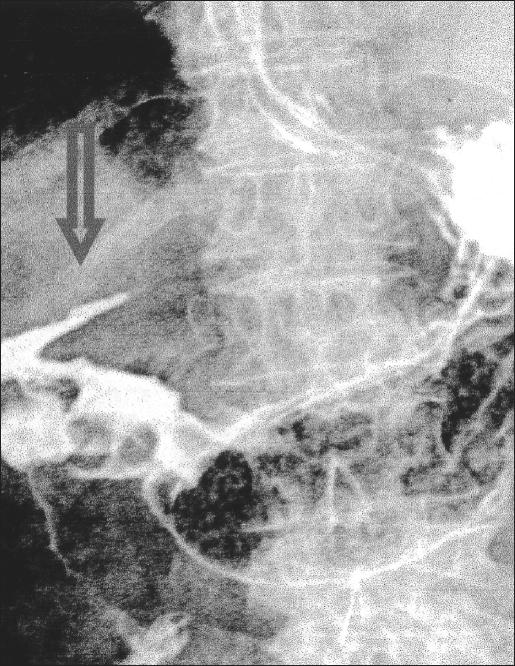

A 75-year-old woman affected by cirrhosis of the liver (Child class C) and chronic gastric ulcer presented with acute abdominal pain. The diagnosis of perforation was made with plain films of the abdomen and computed tomography. Diagnostic laparoscopy showed intense peritonitis due to a perforated ulcer of the anterior gastric wall, 2 cm proximal to the pylorus. Suture closure and placement of an omental patch were performed laparoscopically.

Postoperative recovery was complicated by a minor leak of the gastric suture, managed by total parenteral nutrition. Closure of the gastric wound was demonstrated by Gastrografin studies on the 10th postoperative day. The patient was discharged on the 16th postoperative day. At 3-months follow-up, the patient is alive and free of gastric disease.

一名75岁患有肝硬化(Child C级)和慢性胃溃疡的女性出现急性腹痛。通过腹部平片和计算机断层扫描做出穿孔诊断。诊断性腹腔镜检查显示,幽门近端2厘米处的胃前壁溃疡穿孔导致严重腹膜炎。通过腹腔镜进行缝合关闭和网膜补片放置。

术后恢复因胃缝合处轻微渗漏而复杂化,通过全胃肠外营养处理。术后第10天的泛影葡胺检查证实胃伤口已愈合。患者于术后第16天出院。在3个月的随访中,患者存活且无胃部疾病。